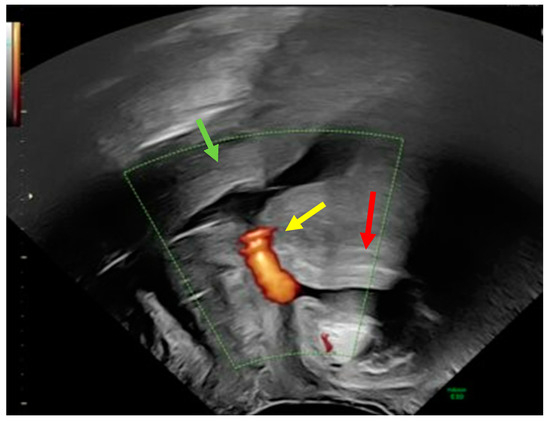

Adhesiolysis revealed a fistula between the urinary bladder and the uterus. The presence of sutures from a previous caesarean section most likely caused this abnormal communication. The abnormal tract between the two organs was removed using partial cystectomy, cystography, and partial myomectomy. Reconstruction was performed using a multilayer technique (Figure 3).

Figure 3.

Multiple layers of sutures of the vesico urinary (black arrow) and uterus (yellow arrow).

An Omentum flap was placed between the uterine body and bladder. The flap was carefully sutured to provide additional support and to promote healing (Figure 4).

Figure 4.

Omentum plastic.